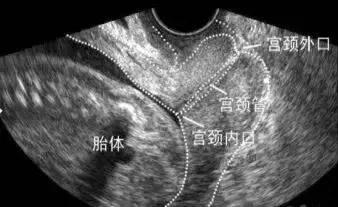

先兆早产:符合早产孕周,虽有上述规律宫缩,但宫颈尚未扩张,经阴道超声测量宫颈管长度≤20 mm即诊断为先兆早产。

1.经阴道超声测量宫颈管长度:在妊娠约14周时,宫颈长度测量才可能具有可重复性。在妊娠16~28周经阴道超声发现宫颈长度缩短(<25 mm)时,早产风险明显增加。